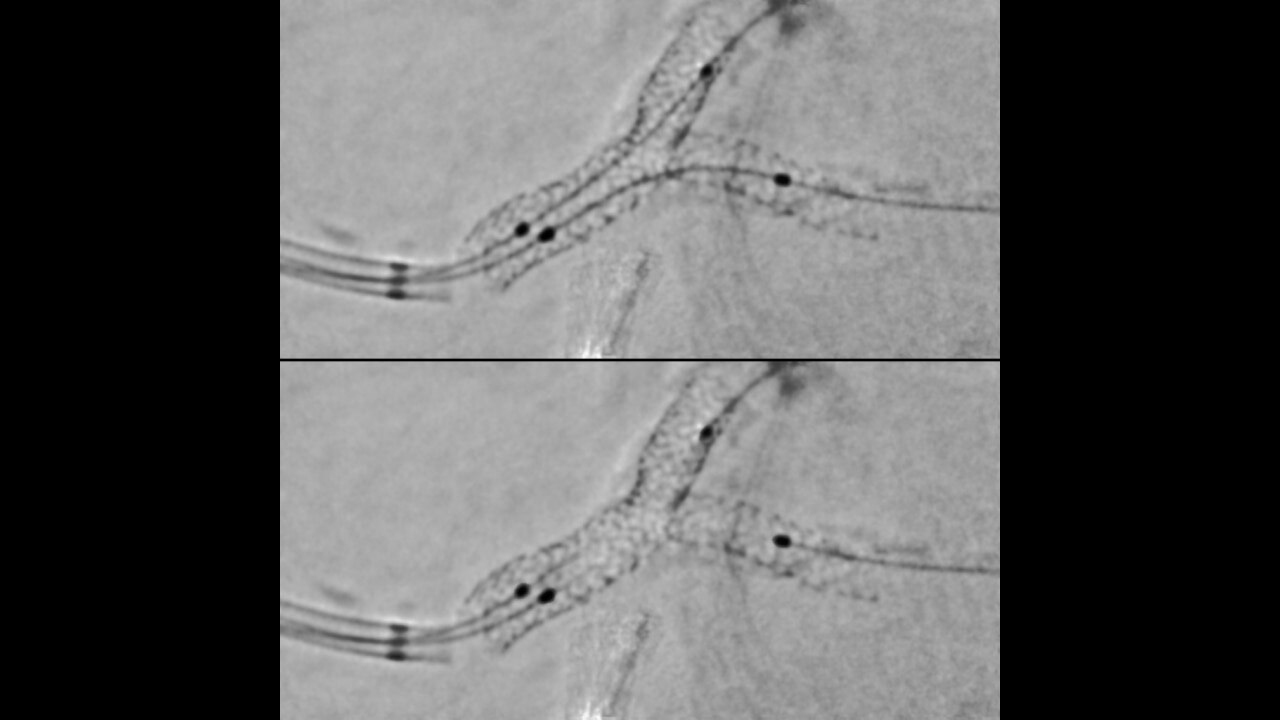

Augmented 2D image guidance

Help to increase positioning accuracy and confidence in multiple stent positioning.

Enhance the visibility of both stents in a bifurcation thanks to our improved StentViz algorithm.

Save time thanks to an automatic single acquisition workflow.

Improve anatomical visibility by up to 85%3,4 in moving arteries at the same radiation dose.